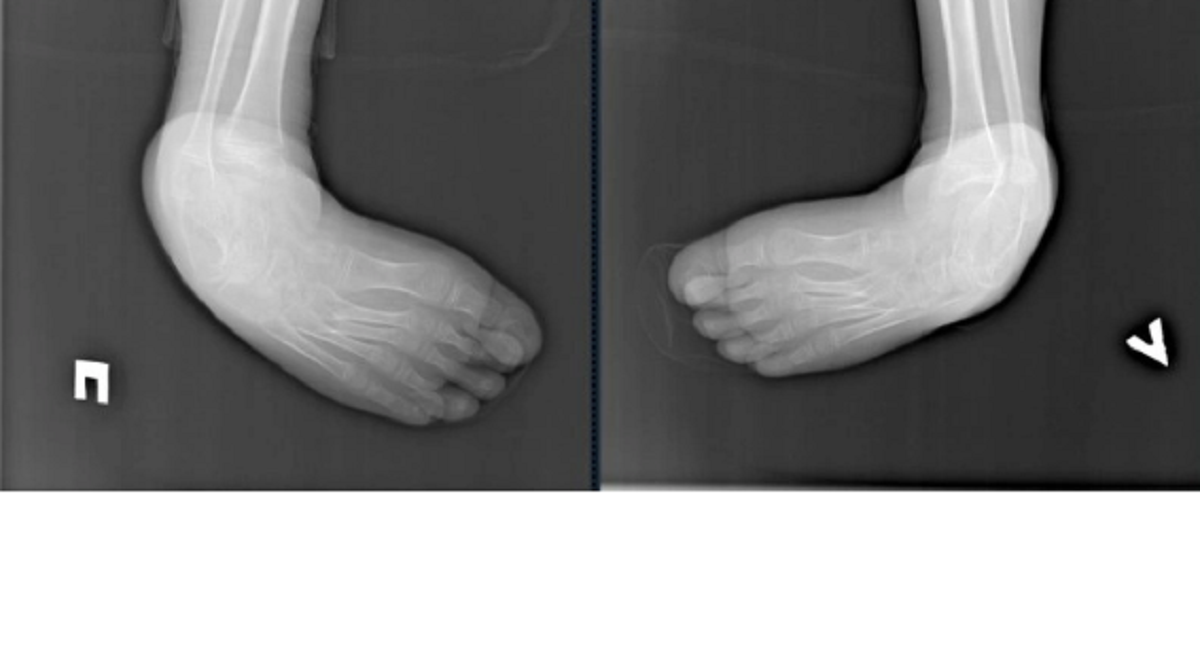

По информации пресс-службы больницы, первая операция на правой стопе была выполнена 19 сентября. После нее пациент восстанавливался дома. Через два месяца хирурги провели вторую операцию. Обе процедуры длились около часа.

Заведующий травматологическим отделением Глеб Большаков подчеркнул в беседе с Irkutskmedia.ru, что сложность операции усугублялась поздним обращением за медицинской помощью, так как подобные деформации обычно корректируются в более раннем возрасте.

Врач отметил, что прогнозы благоприятны при условии продолжения лечения. Хирурги завершили свою часть работы, и теперь важны реабилитация, тренировки и настойчивость мальчика.